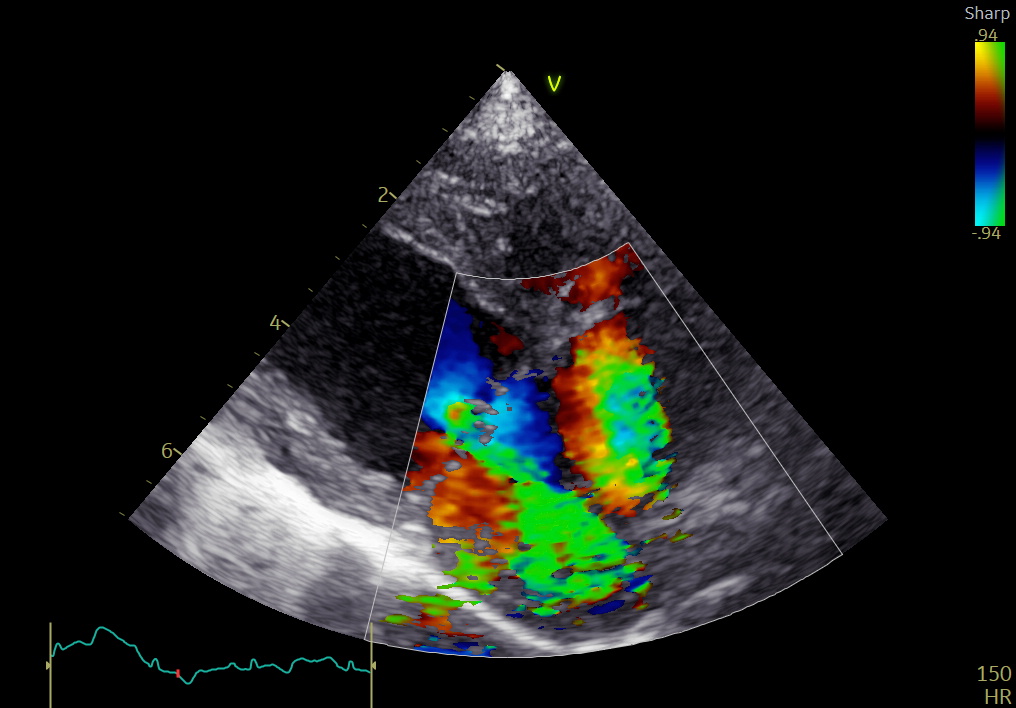

■ 術後経過

術後経過は良好で、大きな合併症は認められませんでした。

術後1か月:

• 僧帽弁逆流は消失

• LA/Ao:1.43

• LVIDDN:1.62

術後3か月:

• LA/Ao:1.29

• LVIDDN:1.40

心拡大は明らかに改善し、内服薬はすべて中止となりました。

術後6か月現在も、臨床徴候なく安定しています。

手術後